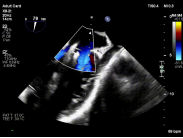

手术中,团队经食管超声心动图(TEE)引导下精准完成房间隔穿刺,为器械操作提供良好空间;建立稳定输送路径,使导向系统与二尖瓣平面充分对齐;利用X-plane及三维超声反复定位脱垂区域,微调器械角度,实现对目标瓣叶的精准抓取;确认夹持质量后释放装置,最终完成修复。

【图片2-5:术中TEE、夹持瞬间、术后效果图】

术后即刻评估显示,患者二尖瓣反流由重度(4+)降至轻度(1+),跨瓣压差维持理想范围,肺静脉血流明显改善,手术取得良好效果。